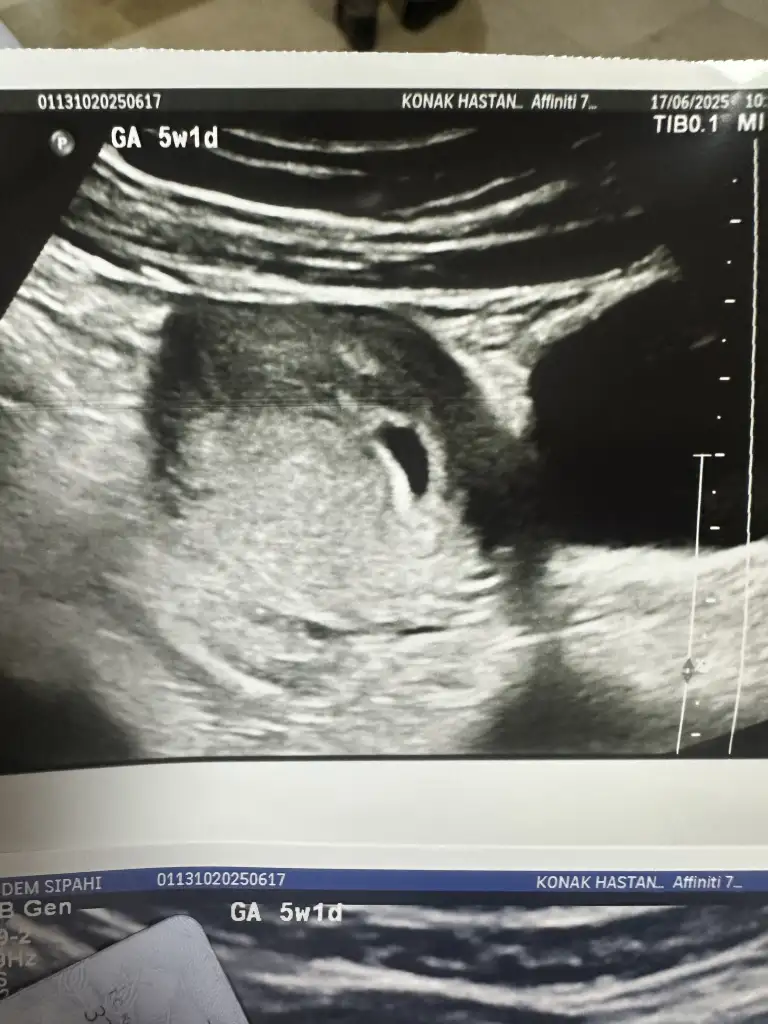

Ayrı haftalarda çekilmiş görüntüler. Karından ultrason. İlki 5hafta 5gün, ikincisi 7hafta 3gün.Nerden bu goruntu? bebek sağdamı soldamı ? bir de ıkı goruntu neden farklı

Sağdamıymış? Cihazı nereye yakın koyuyo doktor?Ayrı haftalarda çekilmiş görüntüler. Karından ultrason. İlki 5hafta 5gün, ikincisi 7hafta 3gün.

Doktor banada bebek sağda, sağa tutunmuş dedi. Resimde tersi çıkıyormuş. Ama bilmiyorum tabisağdan yumurtlamıştım yumurtlama günü pik görünüyorken ovulasyon testinde muayne oldum oradan biliyorum resimde sağdaydı ve tepede sonra tabi ilerleyen haftalarda heryeri geziyor bebek oluşunca

Sağdamıymış? Cihazı nereye yakın koyuyo doktor?Sağda solda gezdiriyordu

Çok bilmiyorum ki. Karında gezdiriyordu cihazıSağdamıymış? Cihazı nereye yakın koyuyo doktor?